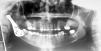

The patient was discharged from hospital 48h after surgery and was allowed to function immediately, with freedom to choose any diet. This case report includes the follow-up until two years after the surgery. Plain film (panoramic) radiographs were obtained at the first post-operative evaluation, at six months and at the following annual visits after surgery, respecting the radiographic principle of ALARA (as low as possible applied radiation justified). In all the radiographic evaluation, non-alterations were reported in the TMJ prostheses or the structures associated (Fig. 3).